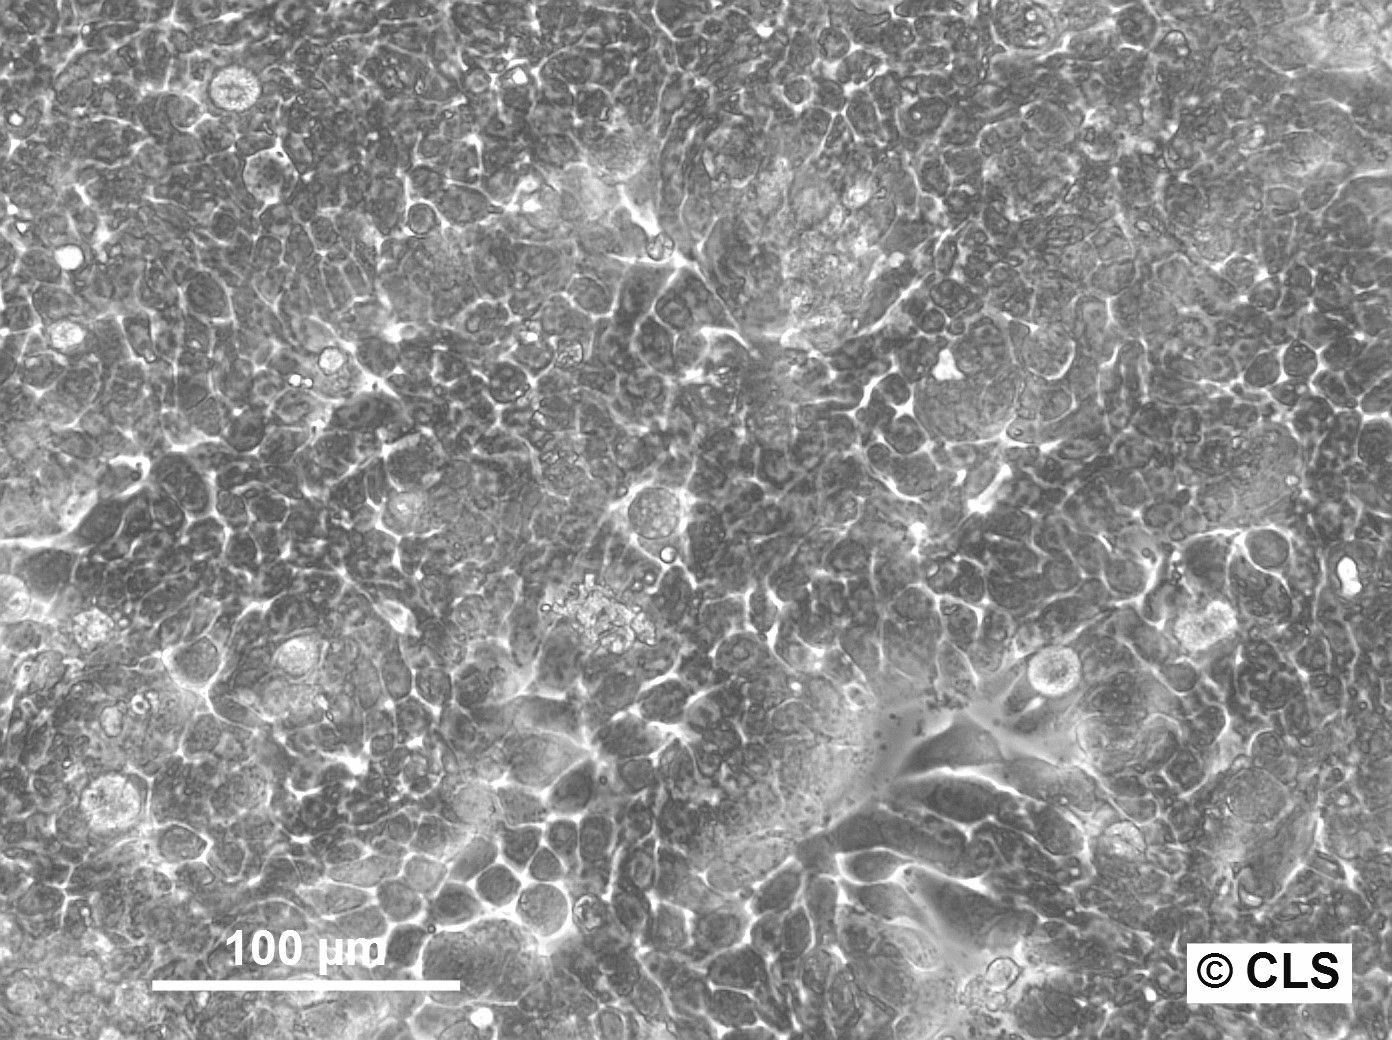

Morphology: Epithelial-like

Growth Properties: Adherent

Description: HuH7 was established in 1982 by Nakabayashi et al. from a 57-year-old Japanese male with well differentiated hepatocellular carcinoma.